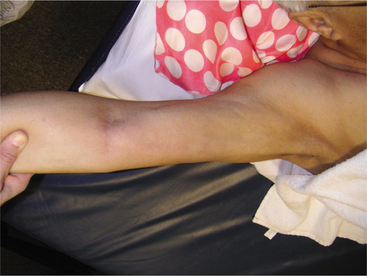

Local metastases by direct extension of the primary disease site may involve the chest wall, ribs, pleura, pulmonary parenchyma, or bronchi and may erode the first and second ribs and associated vertebrae.200 Symptoms associated with metastases can include upper extremity edema, bone pain, jaundice, or weight loss. These findings are rarely the initial complaint.

Bone metastases is especially common affecting the vertebrae, pelvis, ribs, hip, femur, and humerus (see Table 9-2); metastatic spread from breast cancer rarely presents in locations below the elbows and knees. Bone pain and fracture are the most common symptoms of bone metastases.